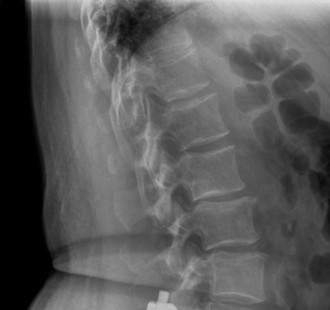

Radiographic and Computed Tomography Evaluation

Initial trauma radiographs demonstrated a loss of anterior and middle column height at L1, with a focal kyphotic deformity. However, plain films are vastly insufficient for definitive surgical planning in thoracolumbar trauma. A high-resolution, fine-cut Computed Tomography (CT) scan of the entire spine was obtained. The CT images confirmed an L1 burst fracture with severe comminution of the vertebral body. Sagittal and axial reconstructions revealed 50% canal compromise secondary to a large retropulsed bone fragment originating from the posterosuperior aspect of the L1 vertebral body. Furthermore, the CT demonstrated 25 degrees of segmental kyphosis measured from the superior endplate of T12 to the inferior endplate of L1.